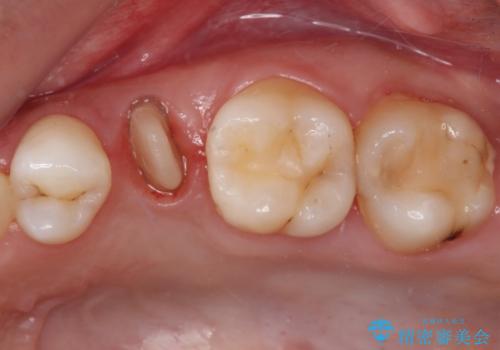

- 根管治療が必要な虫歯を放置した結果、抜歯が必要と診断されたとのことで来院された患者様です。

口腔内の状態やレントゲン写真から判断し、長期的なことを考えると抜歯が無難と思われましたが、それを承知の上で保存するための処置を行うこととしました。

まずは虫歯を除去した上で根管治療を行い、部分矯正により骨内深い位置にまで及んだ健全な部分を引っ張り出すこととしました。

かなり深い位置にまで虫歯が及んでいたため、かなりの量を引っ張り出す必要があり、残された歯根は短く小さい状態となりました。